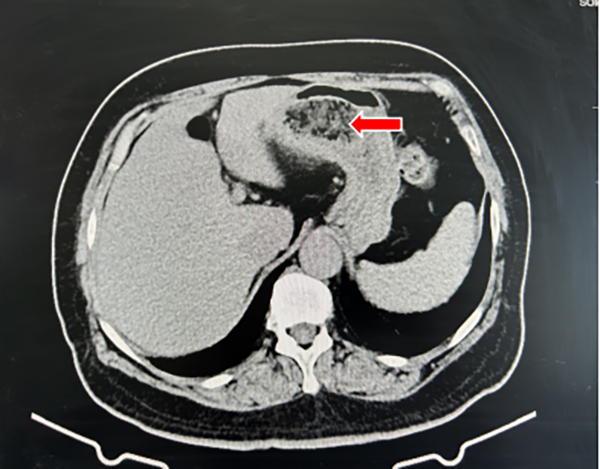

圖 1 腹部CT示胃內(nèi)混雜密度團塊